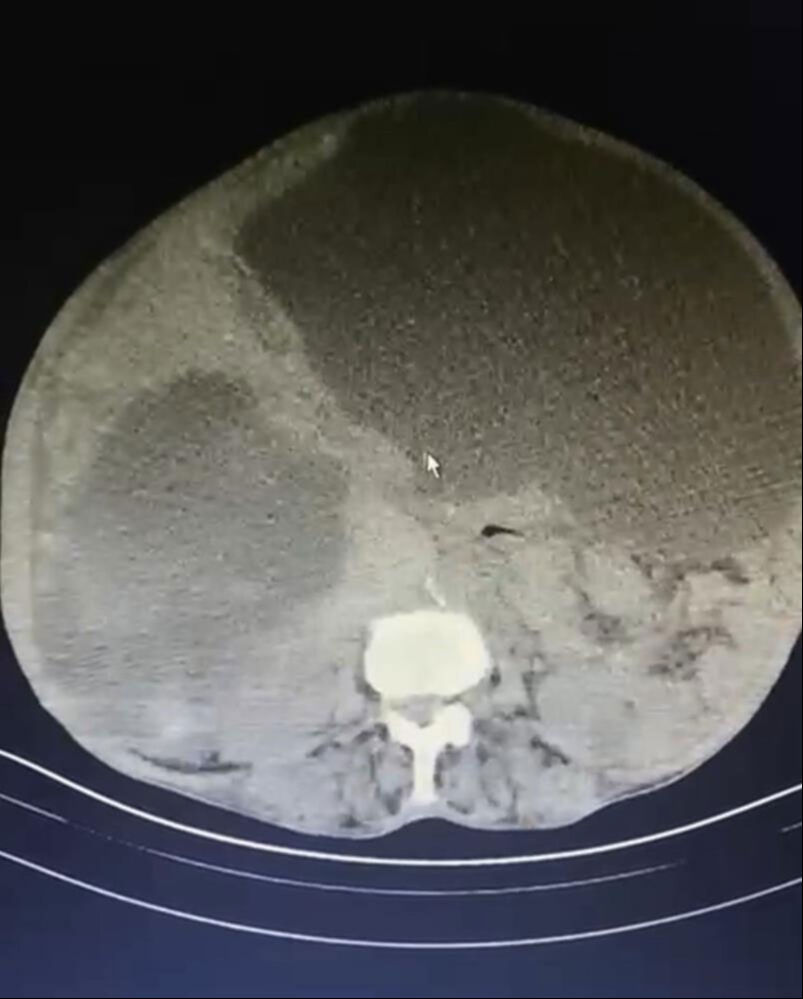

Trabzon’da eşi benzerine rastlanmayan bir operasyon gerçekleşti. Kistlerin büyüklüğü dikkat çekerken Genel Cerrahi Uzmanı Opr. Dr. İsmet Çelik, dünya literatüründe tüm karnı dolduran ve 90 santime ulaşan kist görmediklerini belirterek Taşdelen'e yapılan gerekli tetkikler ve görüntüleme sonucu karaciğerinde üç adet kedi-köpek kisti (hidatik kist) tespit ettiklerini ifade etti.

“Asiye Hanım, maalesef ihmal edilmiş bir hastamız. Bu kist, kedi ve köpeklerin dışkısı ve yediği yiyeceklerle bulaşan bir hastalık. Bu kist, genellikle tesadüfen yakalanabilir. Karaciğere yerleşir. Bu hastamızda da durum öyle olmuş. Ameliyat olamayacağı söylenip eve yollanmış. Bizler detaylandırıp ameliyat kararı aldık. Hastamızın karaciğerinde 3 ayrı kist vardı. Tüm karnı kist ile kaplıydı. 2 tanesinin tamamına çıkardık. Diğerini ise kontrolle alarak içini boşalttık. Dünya literatüründe tüm karnı dolduran ve 90 santime ulaşan kist görmedik.”